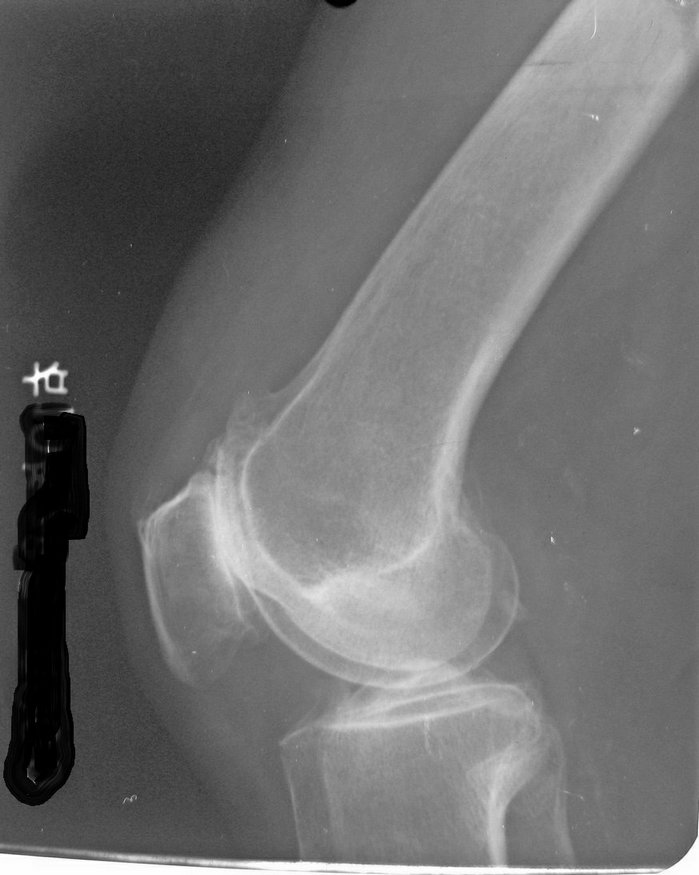

以下是引用拾荒者在2010-7-5 21:08:00的发言:[br]1.膝关节退行性变;2.颈椎未见明显异常。

以下是引用hexue在2010-7-5 22:47:00的发言:[br]1.膝关节退行性变;2.颈椎未见明显异常。 [br] [br]

以下是引用随光逐影在2010-7-6 7:11:00的发言:[br]病例1:双膝关节退行性骨关节病。[br]病例2:1)颈椎未见明确异常。2)一侧下颌智齿横位阻生。